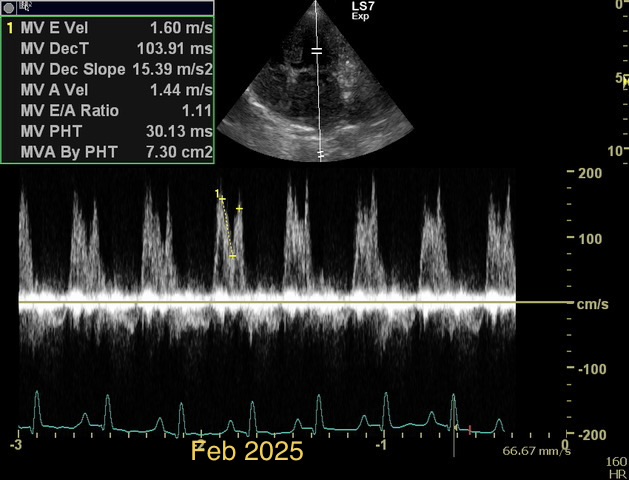

Chronic stage C MVD.TID Pimo and Lasix(high dose), ACEi and Spirono. Doing well. Recheck: Idexx GHP= CBC-NSF ,SDMA 15,BUN 14.1mmol/L, Creat 79umol/L. US: Cornell Indx LVd=1.46(prev2.1), LV septal flattening with diastolic dip,LAAO=2.47,Evel1.45m/s, TVregPG-68mmHg,HV distension-mod ascites.LV and LA underloading via diuretics and PHT (mild PHT past).PHT more pre vs post cap based on small LVsize? Consider Sildenafil/L Arg.Concerned about developing L CHF.Is CHF less likely adding PDE5i with MVD/PHT in underloaded LV than same scenario with vol overloaded LV at similar staging. MVPG=120.3mmHg

Thanks. Not sure if any sig. MV stenosis?? My experience limited.3 PWD from diff times. Ls7 vid. is from 2024,initially thinking reverse remodelling where the lasix lowering preload and Pimo is decreasing LV size via decreased resist/increase cxn while LA no change because it’s a chronic filled remodeled saggy bag receiving Regurge volume??